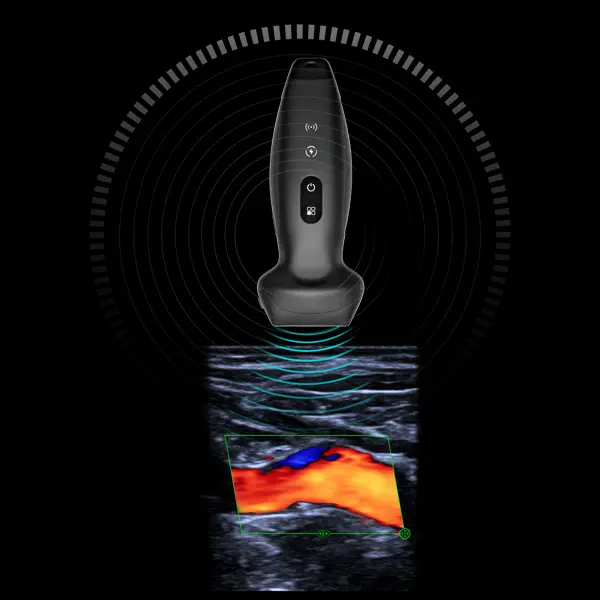

- Безжичен джобен линейно-конвексен ехограф/трансдюсер TE Air e5M Mindray

Безжичен джобен линейно-конвексен ехограф/трансдюсер TE Air e5M Mindray

С портативността си, достъпната цена, лесната употреба и висока ефективност, този джобен ултразвуков апарат позволява бърза диагностика и лечение, като същевременно допринася за подобряване на резултатите за пациентите.

2 в 1 линеен и конвексен трансдюсер, привключване само с един бутон

Чрез интегриране на множество приложения, TE Air e5M предлага сканиране на цялото тяло и се адаптира към различни клинични ситуации. Неговият безжичен дизайн осигурява възможност за извършване на ултразвукови изследвания с високо качество по всяко време и навсякъде. Освен своята универсалност, TE Air e5M предлага и редица интелигентни функции и обучителни инструменти, които повишават увереността и ефективността при работа.

Различни режими на визуализация: B-mode, M-mode, Color Doppler, Power Doppler, PW Doppler

Безжичен, водоустойчив и лесен за подръжка

IP68 ниво на водоустойчивост